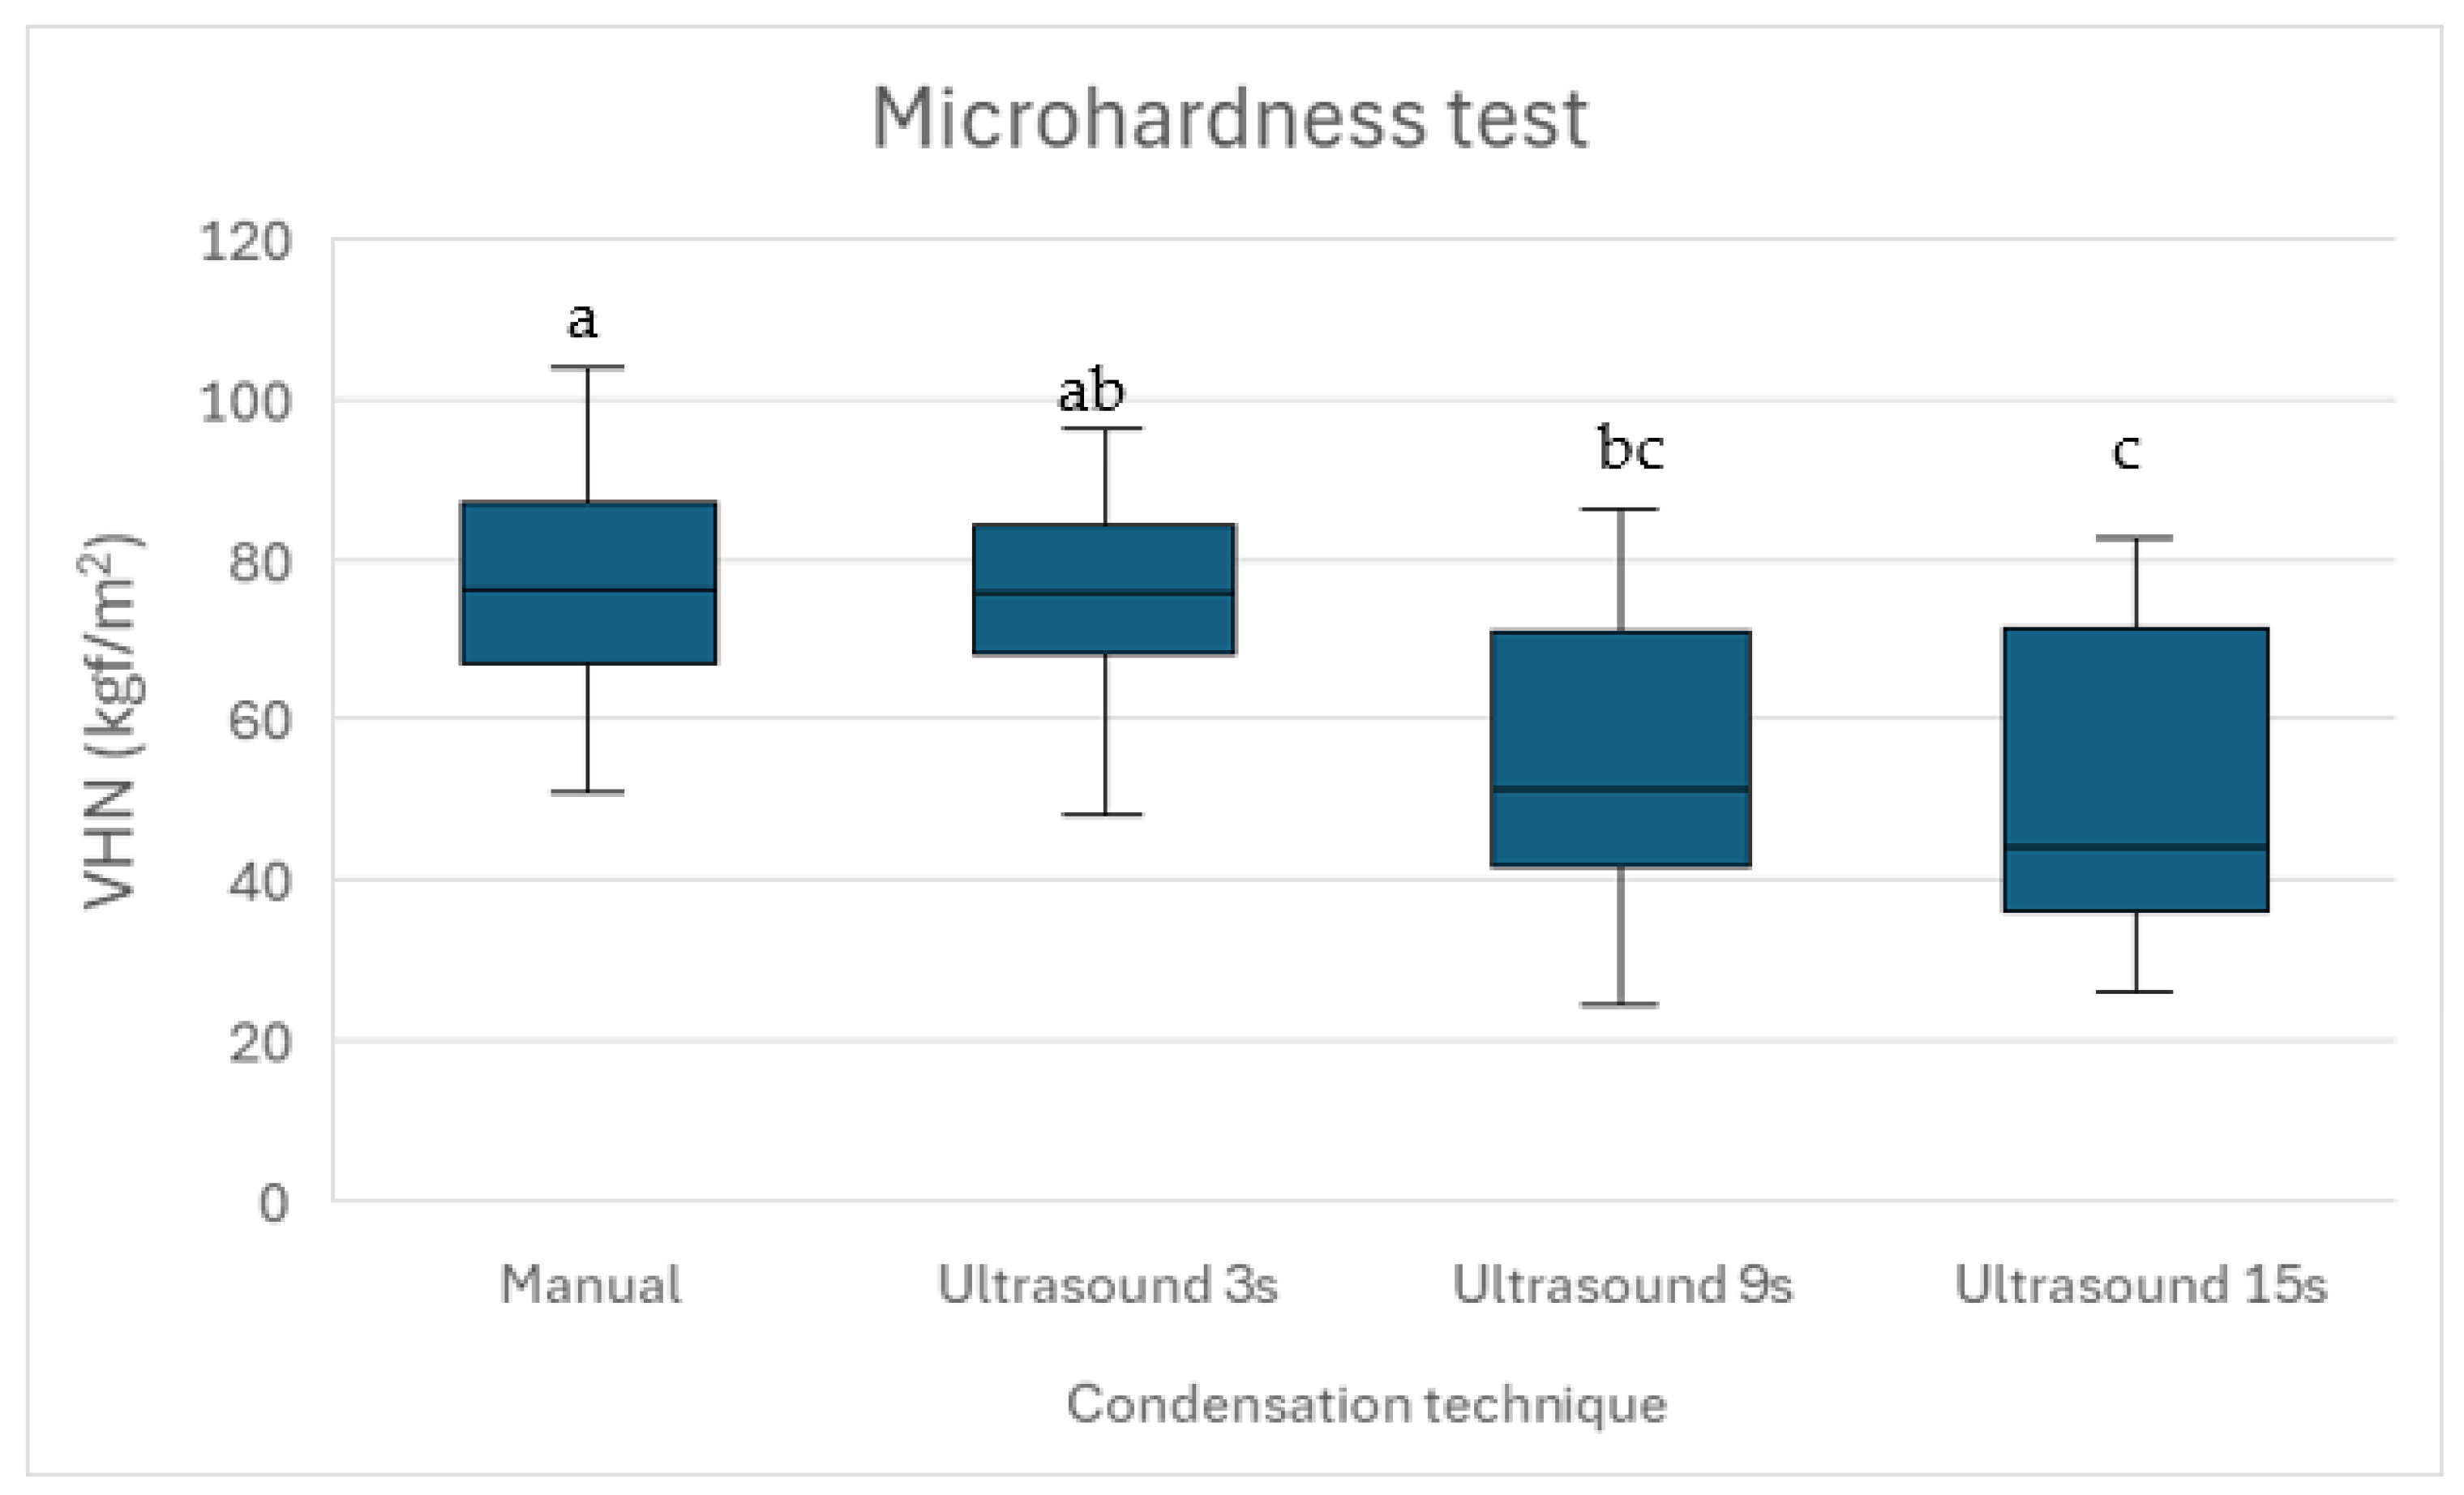

Microhardness, measured using the Vickers test, is critical for apical plug materials, as it correlates with resistance to deformation, durability, and sealing ability, essential for long-term endodontic success [

34]. Biodentine™ exhibits the highest microhardness, followed by Well-Root™ PT, with MTA showing the lowest [

34]. Higher microhardness enhances fracture resistance, marginal adaptation, and resistance to functional stresses [

35]. Brief ultrasonic activation (2–8 s) optimizes MTA’s microhardness by increasing density and reducing voids, but prolonged ultrasonication (>10 s) increases porosity and reduces microhardness [

16,

36]. Biodentine™ and Well-Root™ PT maintain high microhardness, regardless of placement technique [

35].

This is the first study to evaluate the effect of ultrasonic condensation during apical plug formation on the microhardness of premixed bioceramic putty Well-Root™ PT. Microhardness is a crucial indicator of a material’s durability and resistance to deformation. The present study found that manual condensation had the highest microhardness values, consistent with previously reported data [

46]. The microhardness values decreased progressively with longer ultrasonic durations, with Group 4 exhibiting the lowest values (

p < 0.05). Microscopic examination of the indented surfaces (

Figure 1) showed no visible cracking or deformation, supporting the suitability of this load for Well-Root™ PT. However, lower loads (100–500 g) are recommended for some brittle biomaterials to minimize the risk of microcracking [

35], and future studies could validate our findings using a range of loads to ensure measurement reliability. To assess the material’s response to loading and unloading, indentation surfaces were examined microscopically post-testing to evaluate surface integrity and deformation characteristics.

The loading and unloading behavior of Well-Root™ PT, as inferred from indentation surface analysis, indicates that brief ultrasonic activation (3 s) and manual condensation preserve surface integrity, as evidenced by sharper indentation edges and higher microhardness values. Prolonged ultrasonic activation (15 s) likely increases surface porosity, reducing resistance to deformation and contributing to lower microhardness (p < 0.05). These findings underscore the importance of optimizing condensation techniques to maintain surface mechanical properties, which are critical for resisting functional stresses and ensuring a durable apical seal.

Previous studies have reported similar findings for MTA, indicating that brief ultrasonic activation (2–8 s) enhances microhardness by improving material density [

16,

36]. In contrast, prolonged activation (greater than 10 s) decreases microhardness due to increased porosity [

16,

36]. The high microhardness observed in Group 1 may reflect the stable, dense structure achieved through controlled manual condensation, even though this technique resulted in slightly higher void volumes compared to Group 2. The performance of Group 2, which utilized 3 s of ultrasonic activation, effectively balanced low void volumes with relatively high microhardness, indicating its potential as an optimal technique for Well-Root™ PT apical plugs.

Our findings on Well-Root™ PT’s void formation and microhardness can be contextualized by comparing them with those for MTA and Biodentine™, two widely used calcium silicate-based materials for apexification. Similarly to our results, studies on MTA show that brief ultrasonic activation (2–8 s) reduces void formation and enhances microhardness by improving material density, whereas prolonged activation (>10 s) increases porosity and reduces microhardness, aligning with the higher external voids and lower microhardness in our 15-s Ultrasonic group [

16,

36]. However, Well-Root™ PT’s premixed formulation exhibited consistent internal void volumes across all groups (

p > 0.05), unlike MTA, which is more prone to internal voids when manually mixed and condensed due to technique sensitivity [

13,

15]. Biodentine™, noted for high microhardness and low technique sensitivity, maintains superior adaptation to dentin walls regardless of condensation method, outperforming Well-Root™ PT in microhardness (mean VHN: ~85–90 vs. 76.95 for Manual Condensation) but showing comparable sealing ability [

34]. The 3-s Ultrasonic group’s low void volumes and high microhardness (73.11 ± 4.82 VHN) suggest Well-Root™ PT performs comparably to Biodentine™ under optimized conditions, offering clinical advantages like ease of use and no discoloration [

21]. Future studies directly comparing these materials under identical protocols are needed to quantify relative performance in vivo.